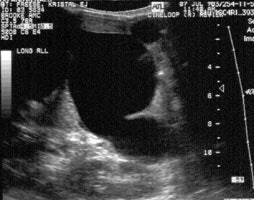

Biliary atresia: The patient presented for evaluation of suspected biliary atresia at 3 months of age. The exam demonstrated delayed, but homogeneous uptake of tracer on early images (click early image to enlarge). No bowel activity can be seen. Delayed images at 24 hours demonstrated persistent hepatic activity, no bowel activity, and bladder activity secondary urinary excretion of the tracer. A shielded image was also obtained to enhance detection of any subtle GI activity. The patient was confirmed to have biliary atresia. |